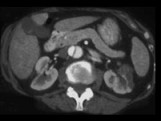

男,54岁,请根据所示图像,选择最可能诊断 ( ) XL-90171.jpg XL-90172.jpg

题型: 多选题 分类: 肾内科

• A.主动脉夹层

• B.左侧肾积水

• C.左侧肾梗死

• D.左侧肾脓肿

• E.左侧肾囊肿